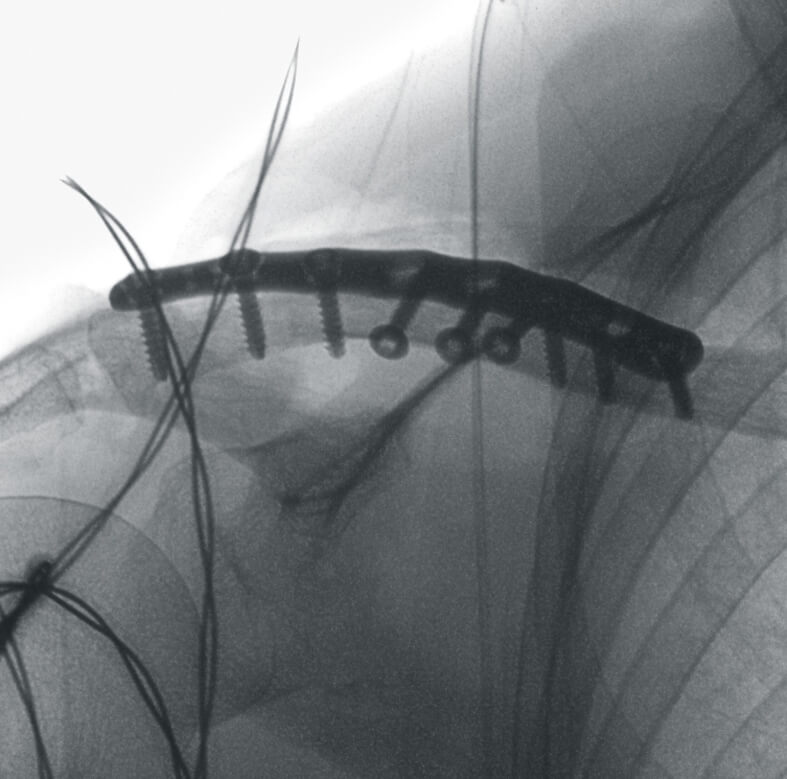

- общая хирургия,

- вертебрология,

Полное отсутствие искажений снимков в сочетании с высоким динамическим диапазоном широко востребованы как при сложных операциях в нейрохирургии, сосудистой хирургии, инвазивной радиологии, так и в гибридных областях применения, а также в ортопедии, травматологии. В сосудистой хирургии особенно важны высокий динамический диапазон и пространственное разрешение, обеспечивающие детальную визуализацию даже мельчайших сосудов. Специализированное программное обеспечение SmartVascular позволяет проводить настройку системы для васкулярных операций и сосудистой хирургии.

Автораспознавание металла

Винты, пластины, импланты и хирургические инструменты автоматически распознаются при попадании в видимое поле аппарата. В этом случае происходит корректировка мощности дозы облучения для улучшения качества снимка.